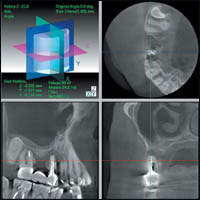

3 DX Accuitomo/FPD после исследования пациента сразу же воспроизводит на экране монитора ИСТИННОЕ трехмерное изображение в трех перпендикулярных друг другу плоскостях.(Рис 2)

Затем возможна реконструкция срезов в вертикальной и горизонтальной плоскости под любым углом к зоне зубочелюстной дуги.

Благодаря этому врач имеет возможность просмотреть изображение более детально (т.е. в трех плоскостях, а также послойно или с необходимым интервалом в режиме видеофильма). Трехмерное изображение 3 DX Accuitomo/FPD открывает новые возможности и перспективы планирования терапевтических, а также хирургических вмешательств в современной стоматологической практике и оториноларингологии (рис. 3).

— позволяет проводить оценку результатов ортопедического и ортодонтического лечения стоматологических пациентов

(рис. 6);